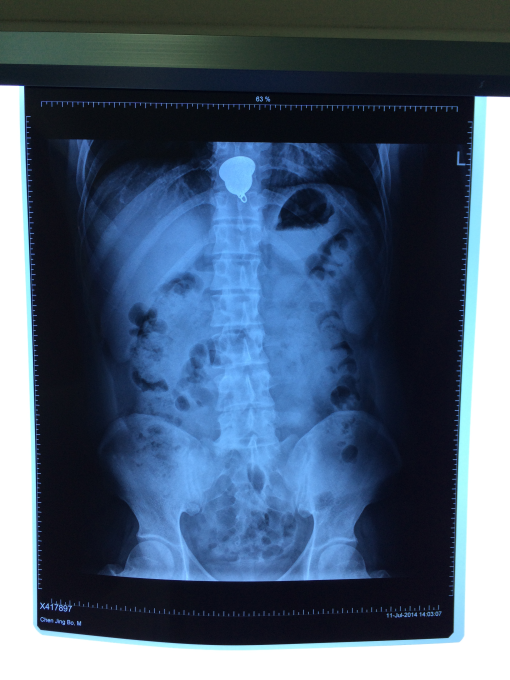

7月11日中午我院住院部消化科接到急诊科电话,一名青年男子突发胸骨后疼痛伴胸闷气急需急会诊,许丰主任赶赴急诊科,追问病史,患者因与家属“怄气”吞服一枚金制挂件,X线片提示金属异物嵌顿于食管,随时有异物致食管穿孔、感染、出血等可能,有急诊内镜下取异物指征,但风险较大,经与患方反复商量后,患方同意行内镜下治疗。术中见一大小约3.5cm金色异物嵌顿于食管下段,许主任迅速用异物钳取出异物,异物为一枚“金佛”,术后患者症状立马缓解。